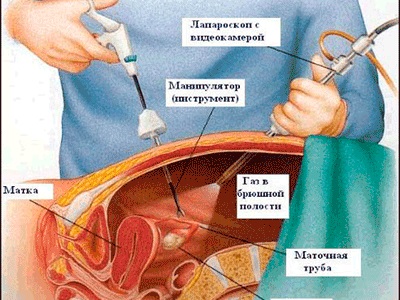

Din cercetarea de baza metodelor de laborator sunt panel hormonal, un tumori asociate markerilor immunoflyurestsentnye reacție la un antigen specific. În ceea ce privește o examinare suplimentară după o rezonanță magnetică a organelor de imagistica poate efectua histerosalpingografie si chirurgie laparoscopica. Mărturie pentru toate metodele prezentate sunt individuale și determinate de către medic.